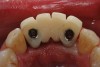

The patient was given postoperative instructions and advised to maintain a soft diet for 6 to 8 weeks to protect the implants. The patient was followed weekly for the first 3 weeks and monthly thereafter. After 4 months of healing, the provisional restoration was removed and the soft tissues were examined. Mature, keratinized gingival tissues were present facially, lingually, and interproximally. Nonkeratinized tissue could be seen at the tissue surfaces of the ovate pontics and in the intrasulcular regions of the implant abutment units. No clinical probing depths beyond 1 mm were found adjacent to the abutments. The healed tissue represented an acceptable clinical result especially in light of the gap that had been present at the time of implant placement (Figure 7A and Figure 7B). Final impressions were made, and the permanent ceramo-metal screw-retained prosthesis was placed within 8 weeks (Figure 8).